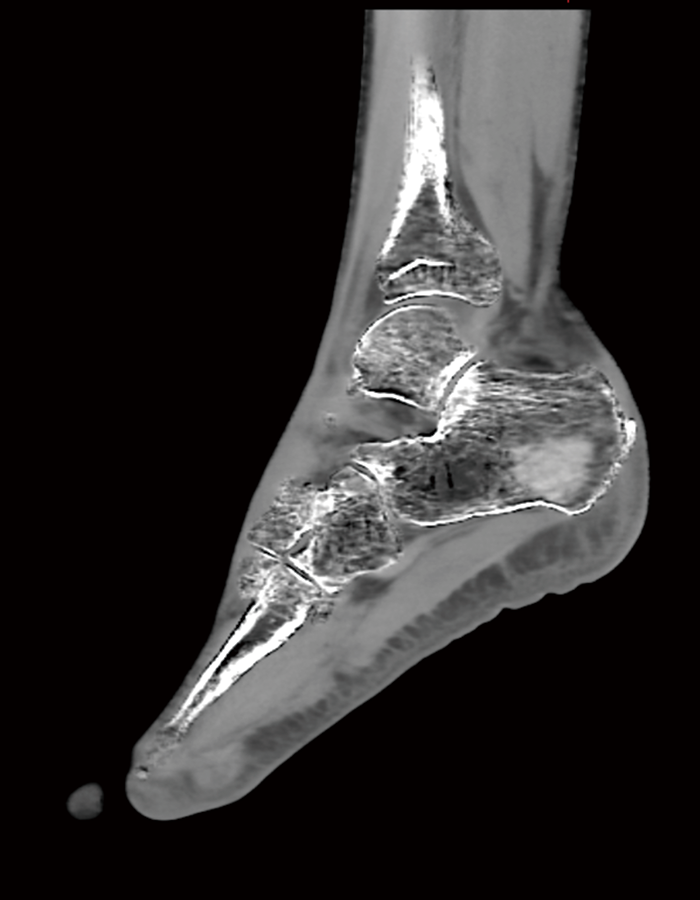

a

踵骨 Dual Energy撮影 骨条件

b

踵骨 Dual Energy撮影 VNCa

図1 踵骨 Dual Energy撮影

a:骨条件 b:VNCa

VNCa画像では骨折が確認できる。